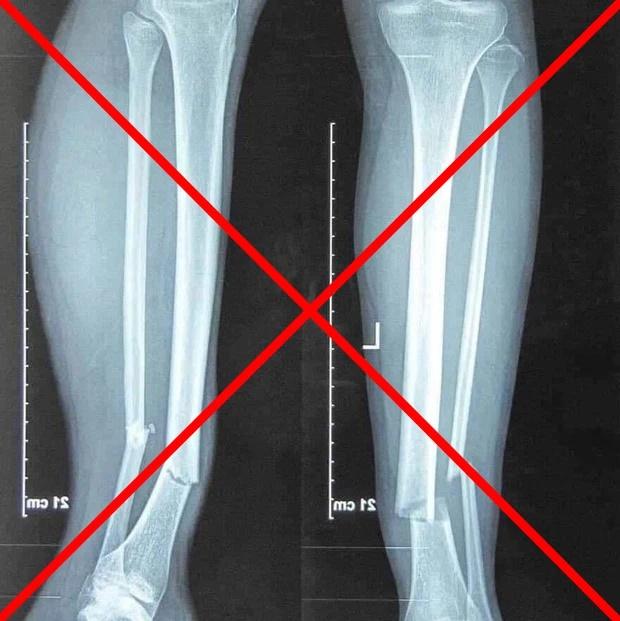

Cũng từ đây, trên mạng xã hội xuất hiện không ít thông tin nhiễu loạn. Trong đó có bức ảnh chụp X-quang phần chân bị gãy được cho là của Hùng Dũng.

Tuy nhiên, phía CLB Hà Nội đã phủ nhận thông tin này. Thực tế đây là bức ảnh chụp của người khác gặp chấn thương gần giống Hùng Dũng.

Bức ảnh chụp X-quang này không phải của Hùng Dũng.